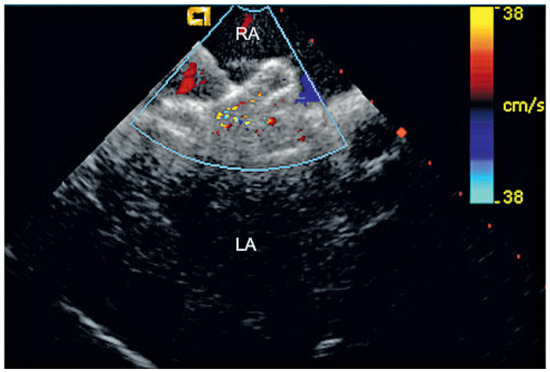

Percutaneous Implantation of an ASD Occluder with Intracardiac Ultrasound

by Frank Enseleit, Oliver Kretschmar and Thomas F. Lüscher

Cardiovasc. Med. 2010, 13(9), 290; https://doi.org/10.4414/cvm.2010.01522 - 15 Sep 2010

A 52-year-old female was admitted for further evaluation of a continuous heart murmur. Transthoracic echocardiography revealed a secundum type atrial septal defect (ASD II) with a size of 13 × 16 mm and considerable left-to-right shunt (Qp/Qs = 2), as well as elevated [...] Read more.

A 52-year-old female was admitted for further evaluation of a continuous heart murmur. Transthoracic echocardiography revealed a secundum type atrial septal defect (ASD II) with a size of 13 × 16 mm and considerable left-to-right shunt (Qp/Qs = 2), as well as elevated pulmonary artery pressure (RV/RA pressure gradient = 38 mm Hg) [...] Full article

Show Figures

Figure 1